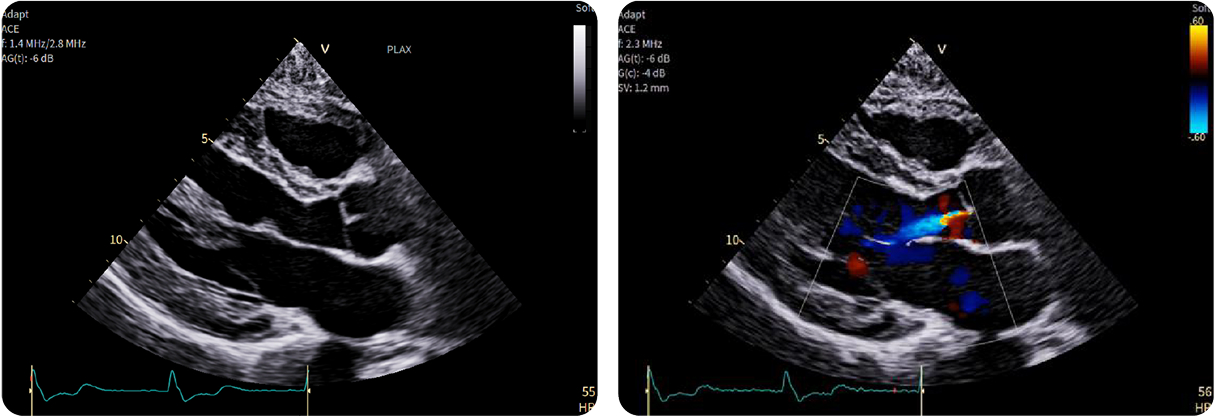

Scopri come le tecnologie di imaging più innovative di GE HealthCare hanno giocato un ruolo chiave nella diagnosi di condizioni cardiache complesse.

1-Beat Cardiac migliora la qualità diagnostica dell’angio-TC coronarica

L’angio-TC coronarica (CCTA) è uno strumento diagnostico essenziale per l’identificazione delle malattie coronariche, ma la sua affidabilità può essere compromessa nei pazienti con frequenza cardiaca elevata. Grazie ai progressi tecnologici, la modalità 1-Beat Cardiac consente ora di ottenere immagini di alta qualità anche in condizioni di elevata frequenza cardiaca.